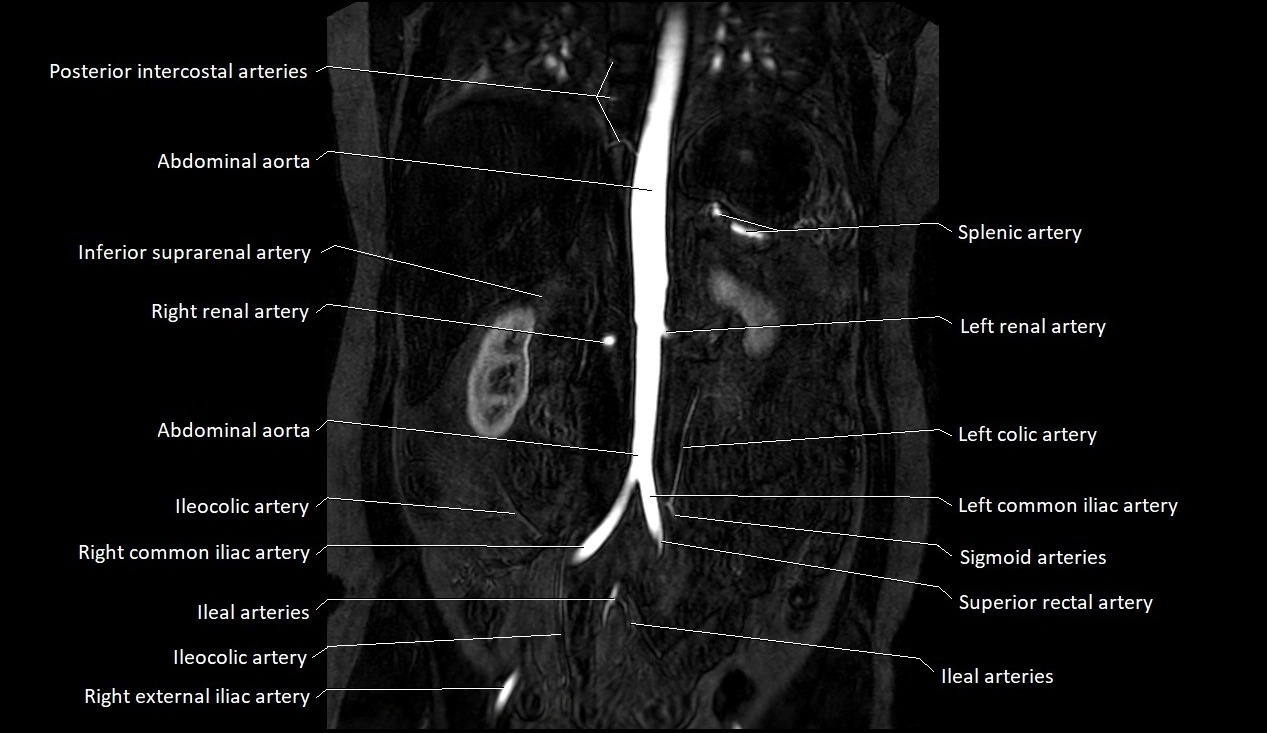

MRI images

image